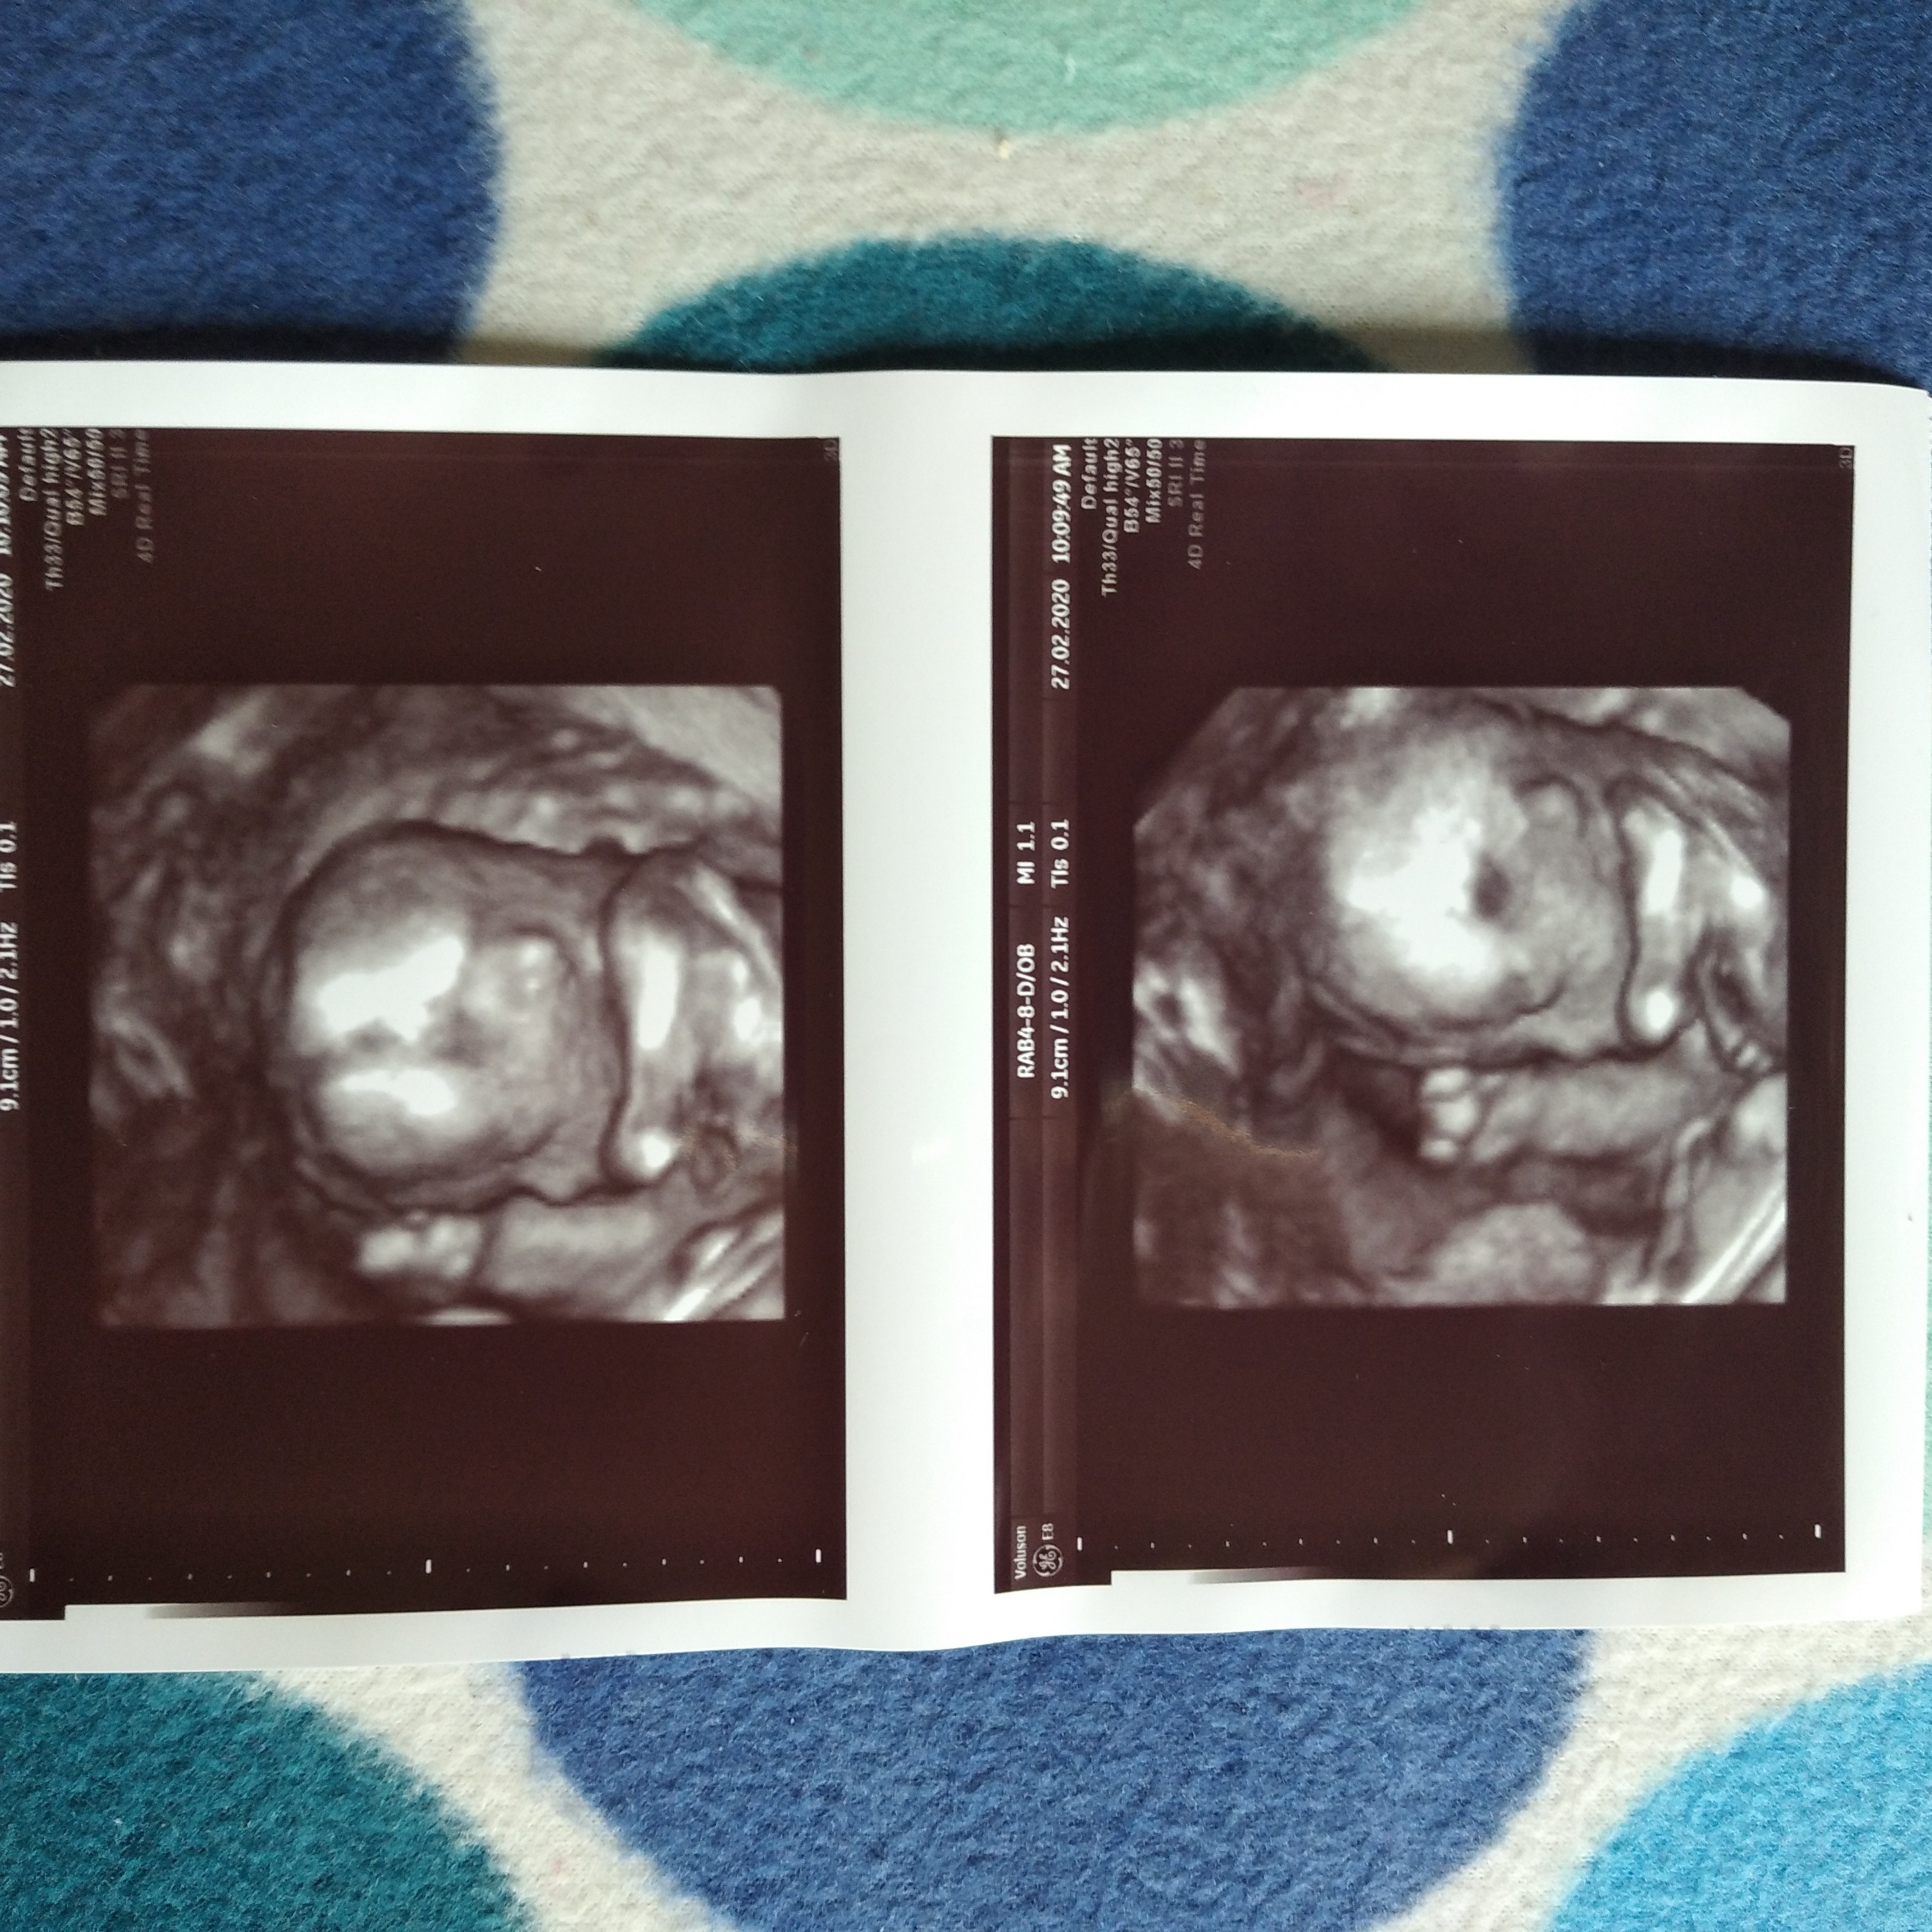

I ja już po wizycie, uwielbiam ten moment jak widzę synusia 😁😁 Malutki zdrowy, waży 176g, tyle że zapomniałam zapytam o cm ale waga ważniejsza 🙂 Przepisał mi jeszcze magnez na te skurcze, pytałam o kwas foliowy bo ja mam w zelazie i witaminach ale mówił że ponoć "dawka już nie ma znaczenia", i że dalej mam brać. W załączniku przesyłam zdj naszego Marcelka 🥰

• IMG_20200227_132133_1.jpg

IMG_20200227_132133_1.jpg

1,6 MB · Wyświetleń: 105